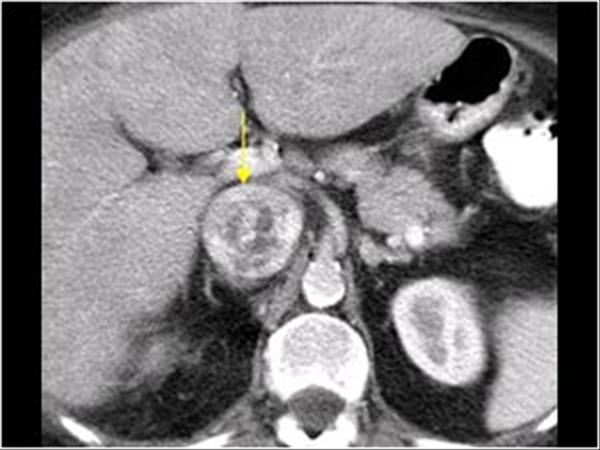

RCC

» Thông tin: Nữ giới – 69 tuổi.

» Lâm sàng: Đái máu.

# Ung thư biểu mô tế bào thận phải (Renal cell carcinoma – RCC) / Huyết khối tĩnh mạch chủ dưới.